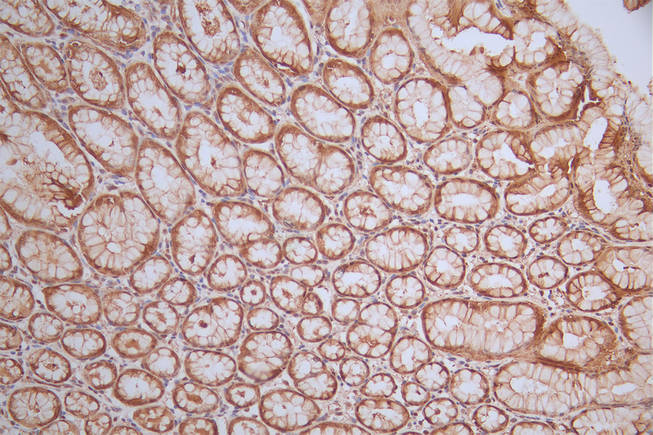

IHC image of CSB-RA984568A0HU diluted at 1:50 and staining in paraffin-embedded human stomach tissue performed on a Leica BondTM system. After dewaxing and hydration, antigen retrieval was mediated by high pressure in a citrate buffer (pH 6.0). Section was blocked with 10% normal goat serum 30min at RT. Then primary antibody (1% BSA) was incubated at 4°C overnight. The primary is detected by a Goat anti-rabbit polymer IgG labeled by HRP and visualized using 0.64% DAB.